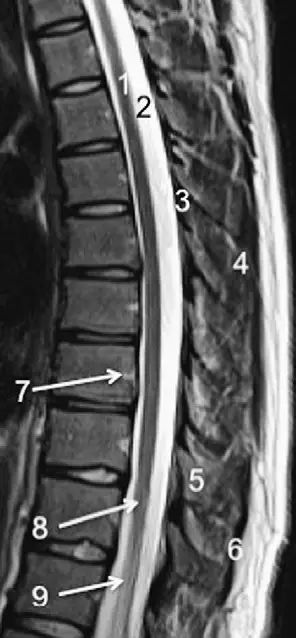

脊柱的MRI解剖

7、棘间韧带:是连于棘突(D9)之间的短韧带。

8、棘上韧带:起于第7颈椎的棘突,延伸至骶骨,参与构成椎骨与骶骨的连结。